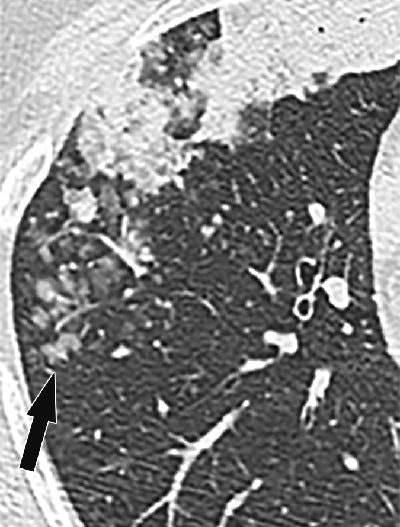

CT features of aerogenous spread of tumor. Image shows primary lung adenocarcinoma in right middle lobe presenting as air-space consolidation in 49-year-old female nonsmoker. Centrilobular nodules (arrow) and acinar opacities are present away from primary lesion in different bronchial territory. Images republished with permission of the American Roentgen Ray Society.